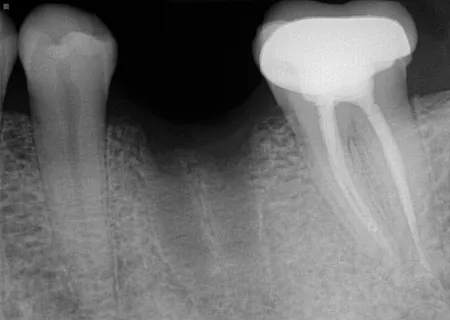

Before

After

Patient’s initial x-rays are for 30 year old male. Recommended tooth 18 molar root canal. Procedure completed on 3-3-14. He was seen for evaluation of another area a follow up x-ray taken 9-16-25 tooth #18.